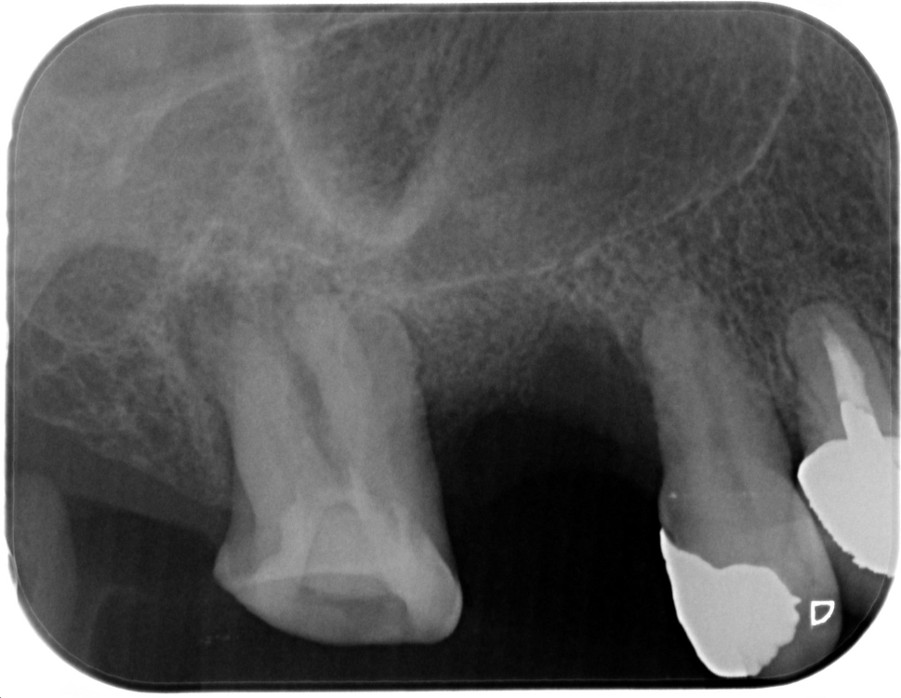

症例2

| 患者様データ | 80代 男性 |

| 来院時の主訴 | 「右上の奥歯が噛むと痛い。」 |

| 医院の診断 | 虫歯の再発、慢性根尖性歯周炎、炎症による歯髄狭窄 |

炎症を起こしてからかなり時間が経っているためか、神経が確認できない程に歯髄狭窄を起こしていました。 ラバーダム防湿とマイクロスコープを使用して丁寧に治療を行いました。 再根管治療のため、殺菌性があり歯を補強することのできる根管充填材料を使用しています。 |